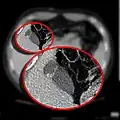

CT scan showing a phrygian cap

CT scan showing a phrygian cap